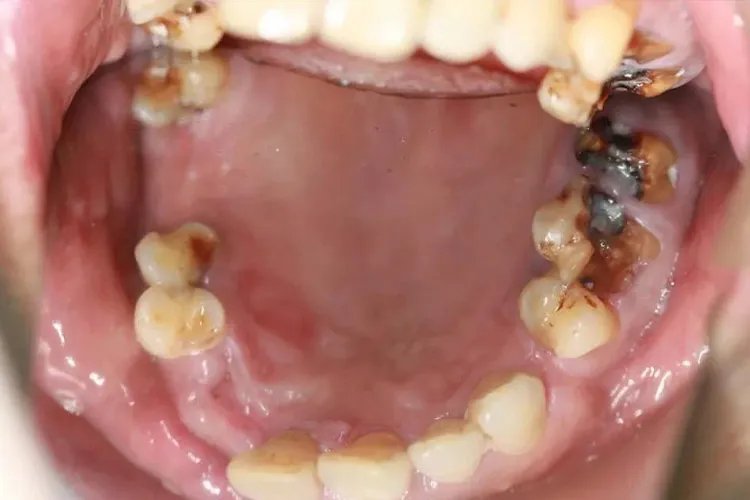

深龋深龋龋损部位牙本质呈明显的黄褐色或深褐色,有较深的龋洞,牙体缺损明显,病变牙本质质地软。当食物嵌塞入龋洞中,或患牙遇冷、热、酸、甜、化学刺激时可出现疼痛,去除刺激后症状立即消失。